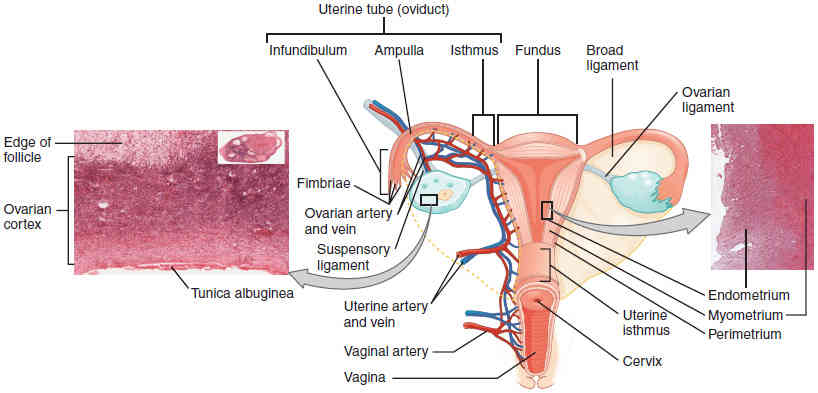

This page is under construction. For now, it is just a resource of the images found in the OpenStax Anatomy and Physiology Handbook. It wil slowly change into a revision tool. Each slide has a number. Use this to refer to the slide. When completed, it will have an unlabelled section, with labelled slides in parallel. On the unlabelled slides, write your answer and use the labelled slide to assess yourself. Keep track by also noting the number on each slide. Improvement at each attempt is important, more so than full marks on a first attempt.